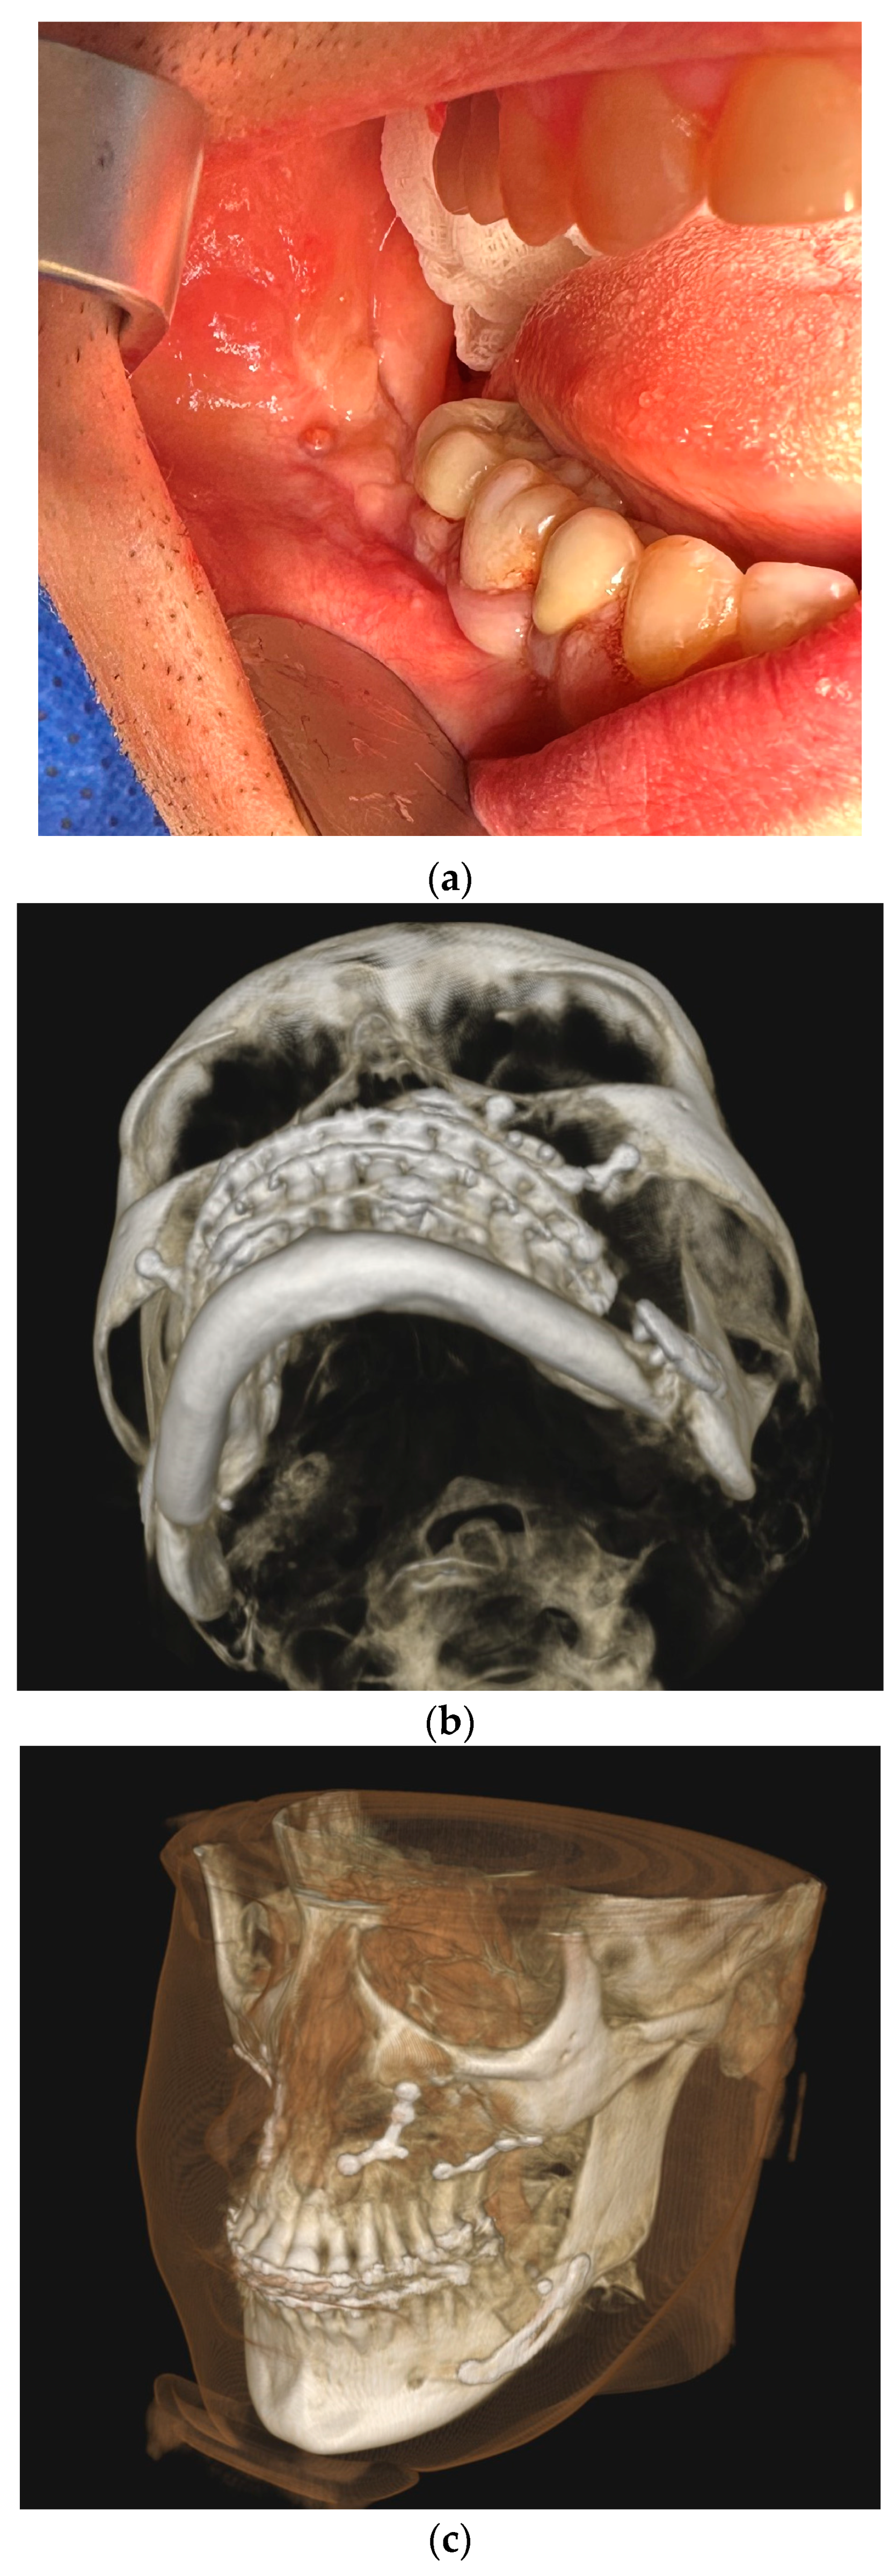

All fixation hardware used in orthognathic procedures was made of titanium (Figure 1).

Figure 1.

Panoramic X-ray with fixation hardware: (a) after BSSO; (b) after BSSO and genioplasty; (c) after Le Fort I osteotomy; (d) after bimax; (e) after bimax with maxillary segmentation and genioplasty.

In the case of sagittal mandibular ramus osteotomy, the typical way to fix the osteotomy fragments was to use one bicortical screw as well as a single plate and monocortical screws on both the right and left side. In a few selected cases, only three bicortical screws were used without a plate, the use of a bicortical screw was abandoned and the fragments were provided fixation using only one plate, and monocortical screws or more than one bicortical screw and a plate were used. Each time it was dictated by individual anatomical and mid-operative conditions. All fixation hardware in the mandible was made with screws that required drilling and were made through an intraoral approach.

In Le Fort I maxillary osteotomy, the osteotomy fragments were typically fixed using 4 plates (most commonly in the shape of the letter “L”; for maxillary segmentation “Y” plates were used) and an appropriate number of monocortical screws. Screws that do not require drilling, i.e., self-drilling screws, were used. In selected situations dictated by anatomical conditions, customized solutions were used in the form of an additional plate, a non-standard shaped plate, or a reduced number of screws.

For genioplasty, dedicated plates with a bridge of appropriate length or two plates bent by the operator according to the planned bone movement were used together with monocortical screws.